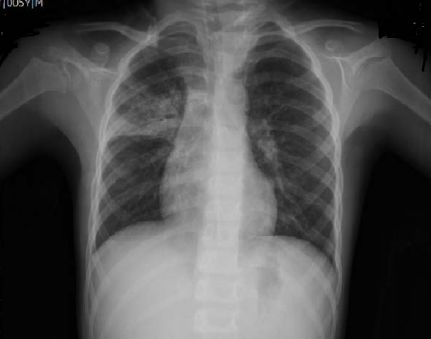

59. 5 歲男童,按期接受疫苗注射,無遺傳疾病。父母帶至急診,主訴一周前 開始咳嗽,且逐漸嚴重伴隨發燒有痰。今日發現病人很虚弱,並抱怨頭痛 和右胸疼痛,且發現孩童胸背有淡紅皮疹,但無腹痛腹瀉的徵狀。胸部 X 光如圖示,在肺右上葉次節肺有斑狀間質侵潤(patchy segmental interstitial infiltrates),近兩側肺門氣管處呈現有間質侵潤斑點(patchy infiltates)。試問感染此肺炎的致病原(pathogen)最可能是?(A)結核桿菌(Mycobacterium tuberculosis)。 (B)黴漿菌(Mycoplasma)。 (C)肺炎球菌(Streptococcus pneumoniae)。 (D)克雷伯氏肺炎菌(Klebsiella pneumoniae)。 (E)流感病毒(Influenza virus)。